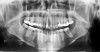

Figure 1b  Panoramic (A) and periapical radiographs (B, C) reveal the absence of periapical rarefaction in the area of the upper right central incisor. However, evidence of apical periodontitis can be seen clearly using the CBCT21 (D, E).

Figure 1b

Figure 1c  Panoramic (A) and periapical radiographs (B, C) reveal the absence of periapical rarefaction in the area of the upper right central incisor. However, evidence of apical periodontitis can be seen clearly using the CBCT21 (D, E).

Figure 1c

In addition to linear accuracy, it has been suggested that CBCT can have diagnostic accuracy with regards to periapical lesions.17-19 In one of these studies,17 periapical lesions were analyzed with CBCT, then surgically excised and biopsied to compare with histology. The authors found comparable results. Although the study showed promising results with CBCT, the researchers conceded that histology remains the gold standard in the diagnostic armamentarium. In another study,19 the ability to identify periapical lesions was assessed using radiographs and spiral CT. With CT, 100% of lesions were identified, while only 78% were identified with radiographs alone. Concomitantly, the location of the lesions proximal to the inferior alveolar nerve was visualized more readily with CT (100% vs 39%). Figure 1A through Figure 1E illustrate a case in which an endodontically treated tooth appeared normal on panoramic and periapical radiographs. Only CBCT showed the presence of apical pathology.6